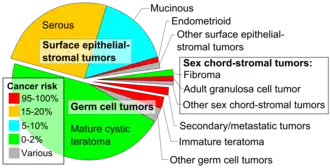

Ovarian cancer is a cancerous tumor of an ovary.[10] It may originate from the ovary itself or more commonly from communicating nearby structures such as fallopian tubes or the inner lining of the abdomen.[3][11] The ovary is made up of three different cell types including epithelial cells, germ cells, and stromal cells.[12] When these cells become abnormal, they have the ability to divide and form tumors. These cells can also invade or spread to other parts of the body.[13] When this process begins, there may be no or only vague symptoms.[1] Symptoms become more noticeable as the cancer progresses.[1][14] These symptoms may include bloating, vaginal bleeding, pelvic pain, abdominal swelling, constipation, and loss of appetite, among others.[1] Common areas to which the cancer may spread include the lining of the abdomen, lymph nodes, lungs, and liver.[15]

The risk of ovarian cancer increases with age. Most cases of ovarian cancer develop after menopause.[16] It is also more common in women who have ovulated more over their lifetime.[17] This includes those who have never had children, those who began ovulation at a younger age and those who reach menopause at an older age.[5] Other risk factors include hormone therapy after menopause, fertility medication, and obesity.[4][6] Factors that decrease risk include hormonal birth control, tubal ligation, pregnancy, and breast feeding.[6] About 10% of cases are related to inherited genetic risk; women with mutations in the genes BRCA1 or BRCA2 have about a 50% chance of developing the disease.[5] Some family cancer syndromes such as hereditary nonpolyposis colon cancer and Peutz-Jeghers syndrome also increase the risk of developing ovarian cancer.[16] Epithelial ovarian carcinoma is the most common type of ovarian cancer, comprising more than 95% of cases.[5] There are five main subtypes of ovarian carcinoma, of which high-grade serous carcinoma (HGSC) is the most common.[5] Less common types of ovarian cancer include germ cell tumors[18] and sex cord stromal tumors.[5] A diagnosis of ovarian cancer is confirmed through a biopsy of tissue, usually removed during surgery.[1]

Ovarian cancers are histologically and genetically divided into type I or type II. Type I cancers are of low histological grade and include endometrioid, mucinous, and clear-cell carcinomas. Type II cancers are of higher histological grade and include serous carcinoma and carcinosarcoma.[28]

Epithelial carcinoma

Sex cord-stromal tumor

Sex cord-stromal tumor, including estrogen-producing granulosa cell tumor, the benign thecoma, and virilizing Sertoli-Leydig cell tumor or arrhenoblastoma, accounts for 7% of ovarian cancers. They occur most frequently in women between 50 and 69 years of age but can occur in women of any age, including young girls. They are not typically aggressive and are usually unilateral;[26] they are therefore usually treated with surgery alone. Sex cord-stromal tumors are the main hormone-producing ovarian tumors.[32]

Germ cell tumor

Germ cell tumors of the ovary develop from the ovarian germ cells.[70] Germ cell tumor accounts for about 30% of ovarian tumors, but only 5% of ovarian cancers, because most germ-cell tumors are teratomas and most teratomas are benign. Malignant teratomas tend to occur in older women, when one of the germ layers in the tumor develops into a squamous cell carcinoma.[26] Germ-cell tumors tend to occur in young women (20s–30s) and girls, making up 70% of the ovarian cancer seen in that age group.[33] Germ-cell tumors can include dysgerminomas, teratomas, yolk sac tumors/endodermal sinus tumors, and choriocarcinomas, when they arise in the ovary. Some germ-cell tumors have an isochromosome 12, where one arm of chromosome 12 is deleted and replaced with a duplicate of the other.[26] Most germ-cell cancers have a better prognosis than other subtypes and are more sensitive to chemotherapy. They are more likely to be stage I at diagnosis.[32] Overall, they metastasize more frequently than epithelial ovarian cancers. In addition, the cancer markers used vary with tumor type: choriocarcinomas are monitored with beta-HCG and endodermal sinus tumors with alpha-fetoprotein.[26]